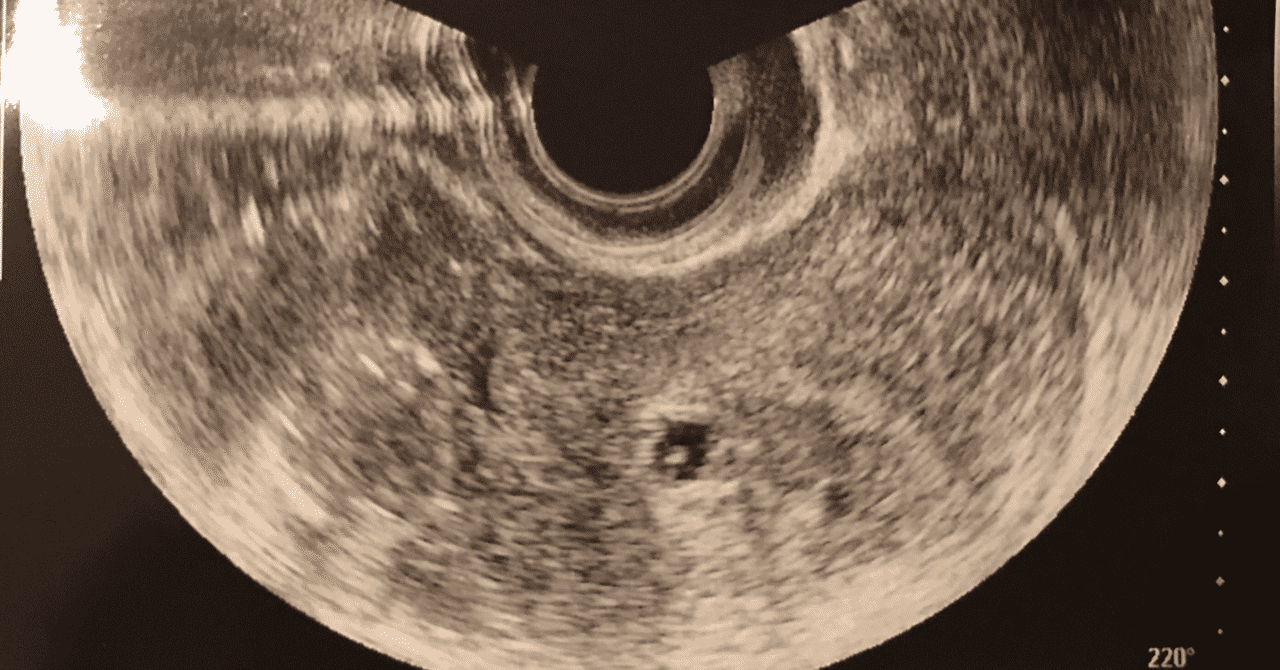

妊娠6週1日 6w1d の超音波 エコー 写真

妊娠6w1dのエコー写真 ページ3